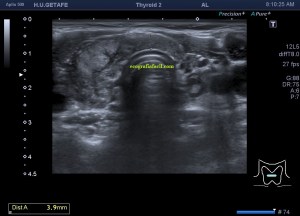

Era un nódulo hiperecogénico en el contexto de la tiroiditis en el estudio de una ecografía tiroidea.

Te enseño las imágenes, típicas de una exploración tiroidea de protocolo con semiología de tiroiditis.

De la imagen 1 a 7 el protocolo habitual, el estudio particular del nódulo con medidas y aplicación del doppler demuestra el aspecto típico del Caballero Blanco.

De la 8 a la 11 estudio con Doppler.

La imagen 12 y 13 están adquiridas con una sonda de 18 Mhz.

En la 14 un ganglio reactivo con medidas respetadas.

El el 15 tienes un vídeo de un corte axial de El Caballero Blanco.

Resumen de las imágenes que has visto en el caso de hoy:

1. Hipoecogenicidad del parénquima

2. Heteroecogenicidad

3. Múltiples nódulos hipoecoicos muy pequeños

4. Doppler Color y Doppler Power aumentado de tamaño en el nódulo

Este es el aspecto ecográfico descrito anteriormente de la patología que habitualmente puede albergar el nódulo del que trata hoy el post y que no es otra que la de la Tiroiditis de Hashimoto.

El Caballero blanco, recibe el nombre debido a su semiología hiperecogénica, homogénea y solitaria circunscrito en la patología referida con anterioridad, puede aparecer en esta patología de forma benigna o degenerar en otro tipo de patología a formas malignas como el linfoma tiroideo.